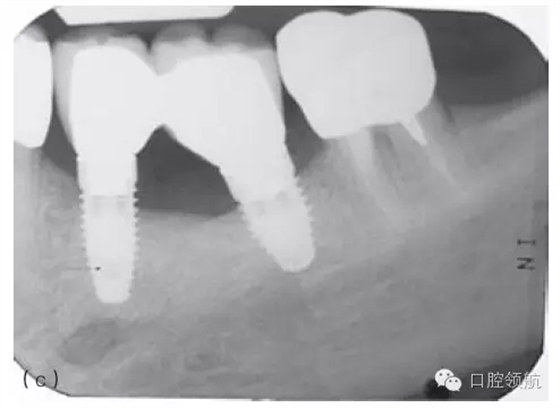

因種植體裝置界面的扭矩可能會(huì)使平臺(tái)連接出現(xiàn)潛在的變形,故應(yīng)注意使該扭矩最小化。Ⅳ類(lèi)骨植入種植體時(shí)要優(yōu)先在骨上敲打擠壓而不是依靠種植體來(lái)擠壓骨洞。許多廠家會(huì)提醒不要超過(guò)手術(shù)操作時(shí)推薦的扭矩,以減小折斷的可能性(圖5.3a~c)。

圖5.3 (a)Ⅰ類(lèi)骨中的種植體內(nèi)連接和界面破損的影像學(xué)表現(xiàn)。(b)取出種植體,發(fā)現(xiàn)沿著種植體平臺(tái)的損壞。(c)在重新放置的種植體上行聯(lián)冠修復(fù)完成2年后的影像學(xué)表現(xiàn)。